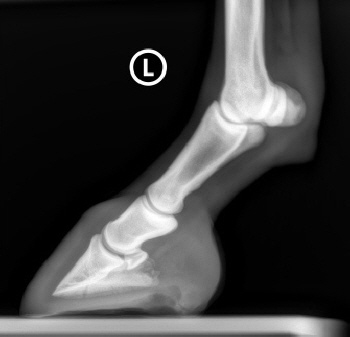

Röntgenbilder akuter- und chronischer Hufrehehufe vorher und nachher

Nachstehend stellen wir einige Röntgenbilder von Hufrehepferden ins Netz, welche das Vorher und das Nachher zeigen. Wir möchten damit aufzeigen, dass durch eine richtige Hufbearbeitung ein Hufbein wieder in eine korrekte Lage innerhalb der Hornkapsel zu liegen kommen kann.

In besonders schweren Fällen wurde doch zumindest eine Optimierung angestrebt.

vorher